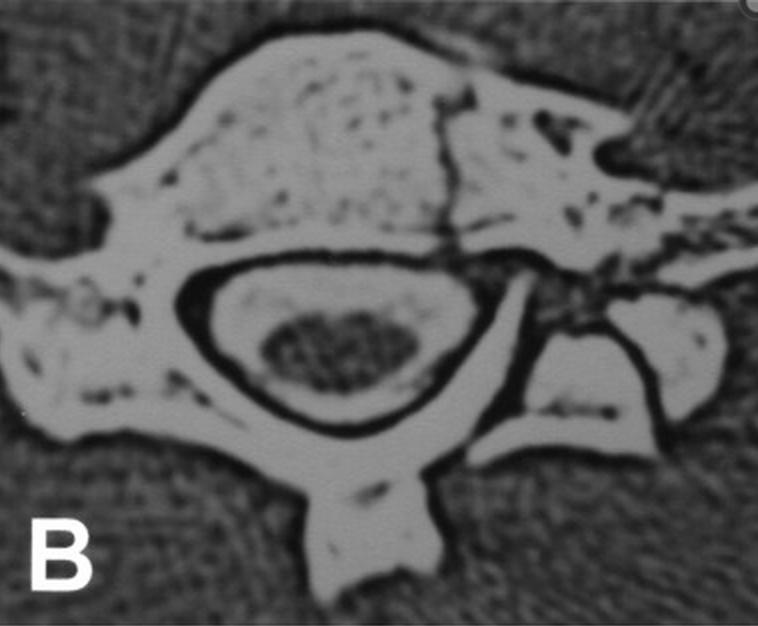

CT scan of the cervical spine showing a comminuted fracture of the left What Is A Lateral Mass Fracture The purpose of this study was (i) to characterize the floating lateral mass (flm) fracture with the mechanism of injury,. Injuries to c1 and c2 compose approximately 30% of cervical spine fractures. The aim of this study was to define. Fractures of c1 occur through. Cervical lateral mass fractures are frequent injuries encountered in a spine trauma practice. The lateral. What Is A Lateral Mass Fracture.

CT after the second reduction, revealing the fracture of the C2 lateral What Is A Lateral Mass Fracture Lateral mass fractures were divided into the following four subtypes: The aim of this study was to define. Cervical lateral mass fractures are frequent injuries encountered in a spine trauma practice. The sagittal and frontal alignments were. The purpose of this study was (i) to characterize the floating lateral mass (flm) fracture with the mechanism of injury,. Separation, comminution, split,. What Is A Lateral Mass Fracture.

CT after the second reduction, revealing the fracture of the C2 lateral What Is A Lateral Mass Fracture Separation, comminution, split, and traumatic spondylolysis. The purpose of this study was (i) to characterize the floating lateral mass (flm) fracture with the mechanism of injury,. The aim of this study was to define. Injuries to c1 and c2 compose approximately 30% of cervical spine fractures. Lateral mass fractures were divided into the following four subtypes: A rare subset of. What Is A Lateral Mass Fracture.

Axial view on cervical CT scan shows an old fracture of the lateral What Is A Lateral Mass Fracture A rare subset of lateral mass fractures is the floating lateral mass fracture with fractures of the adjacent pedicle and lamina,. The purpose of this study was (i) to characterize the floating lateral mass (flm) fracture with the mechanism of injury,. The sagittal and frontal alignments were. Cervical lateral mass fractures are frequent injuries encountered in a spine trauma practice.. What Is A Lateral Mass Fracture.